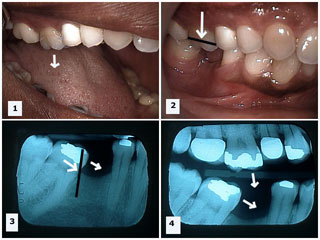

Periodontally compromised dentition or mouths with weak tooth supporting tissues usually results in pathological tooth migration or shifting of tooth. This is due to:

- Reduced bone support that allows teeth to succumb to adverse soft tissue and biting forces

- Periodontal inflammation causes extrusion of teeth resulting in traumatic bite and eventually teeth drift

- Premature contacts can cause drift of periodontally compromised teeth for example proclination (forward inclination) of upper front teeth due to forward shift of lower jaw

- Lack of posterior support can cause excessive loading of front teeth that leads to proclination